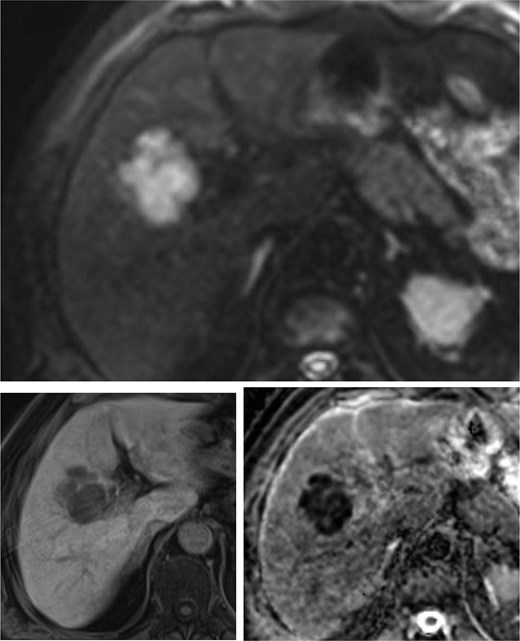

A CT scan unexpectedly revealed a new lesion suspicious for malignancy in liver segments V and VI. Magnetic resonance imaging (MRI) confirmed a well-defined mass in the right hepatic lobe, consistent with metastasis from the known squamous cell carcinoma of the lung (Fig. 1). The pulmonary tumor board recommended surgical resection of the solitary centrally located hepatic metastasis in the right lobe with curative intent.

MRI of the liver with single poly-lobulated, smoothly delineated mass in the right liver lobe.